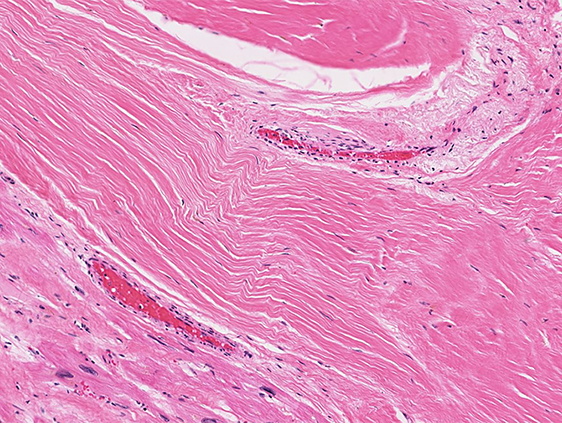

If the body is unable to regenerate after an injury, repair leads to scarring

Scarring occurs in cases where injuries are severe (disrupting stem cells and/or tissue architecture), or the regenerative capacity of the damaged organ is low

Examples of this process include things like deep lacerations (that leave a scar!), infarcts, and cirrhosis (fibrosis of the liver due to longstanding injury)

• Scar: mature collagen that is the end state of the repair process